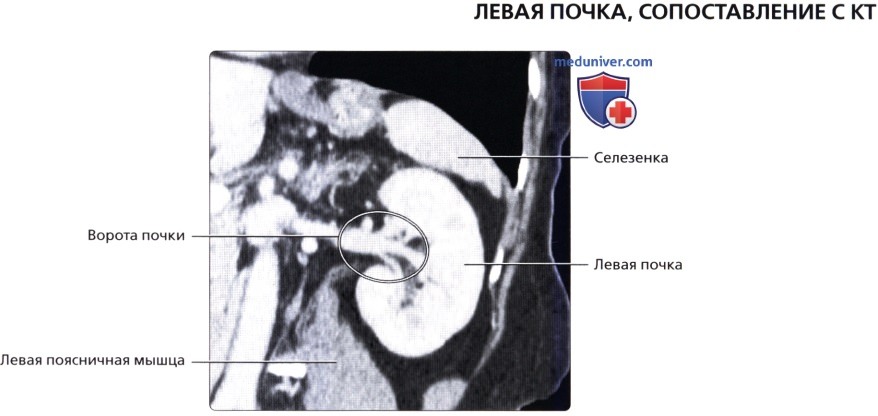

а) Анатомия почек:

2. Топографическая анатомия почки:

• Лежат в забрюшинном пространстве, окружены почечной фасцией (фасция Героты)

• У взрослого каждая почка около 9-14 см в длину и 5 см в ширину

• Обе почки лежат «на» квадратных мышцах поясницы, латеральнее поясничных мышц

б) Лучевая анатомия почки:

1. Обзор:

• Забрюшинные структуры бобовидной формы с четким контуром, смещающиеся при дыхании

• Левая почка:

о Ее труднее визуализировать из-за газа в тонкой кишке и в селезеночном изгибе ободочной кишки

о Обычно левую почку проще визуализировать, используя заднебоковой эхографический доступ и попросив пациента немного повернуться вправо приподняв левый бок

о В сложных случаях полностью переверните пациента в положение лежа на правом боку, подложите подушку под его правый бок и попросите его поднять левую руку над головой:

— Для исследования верхнего полюса левой почки можно использовать селезенку как акустическое окно